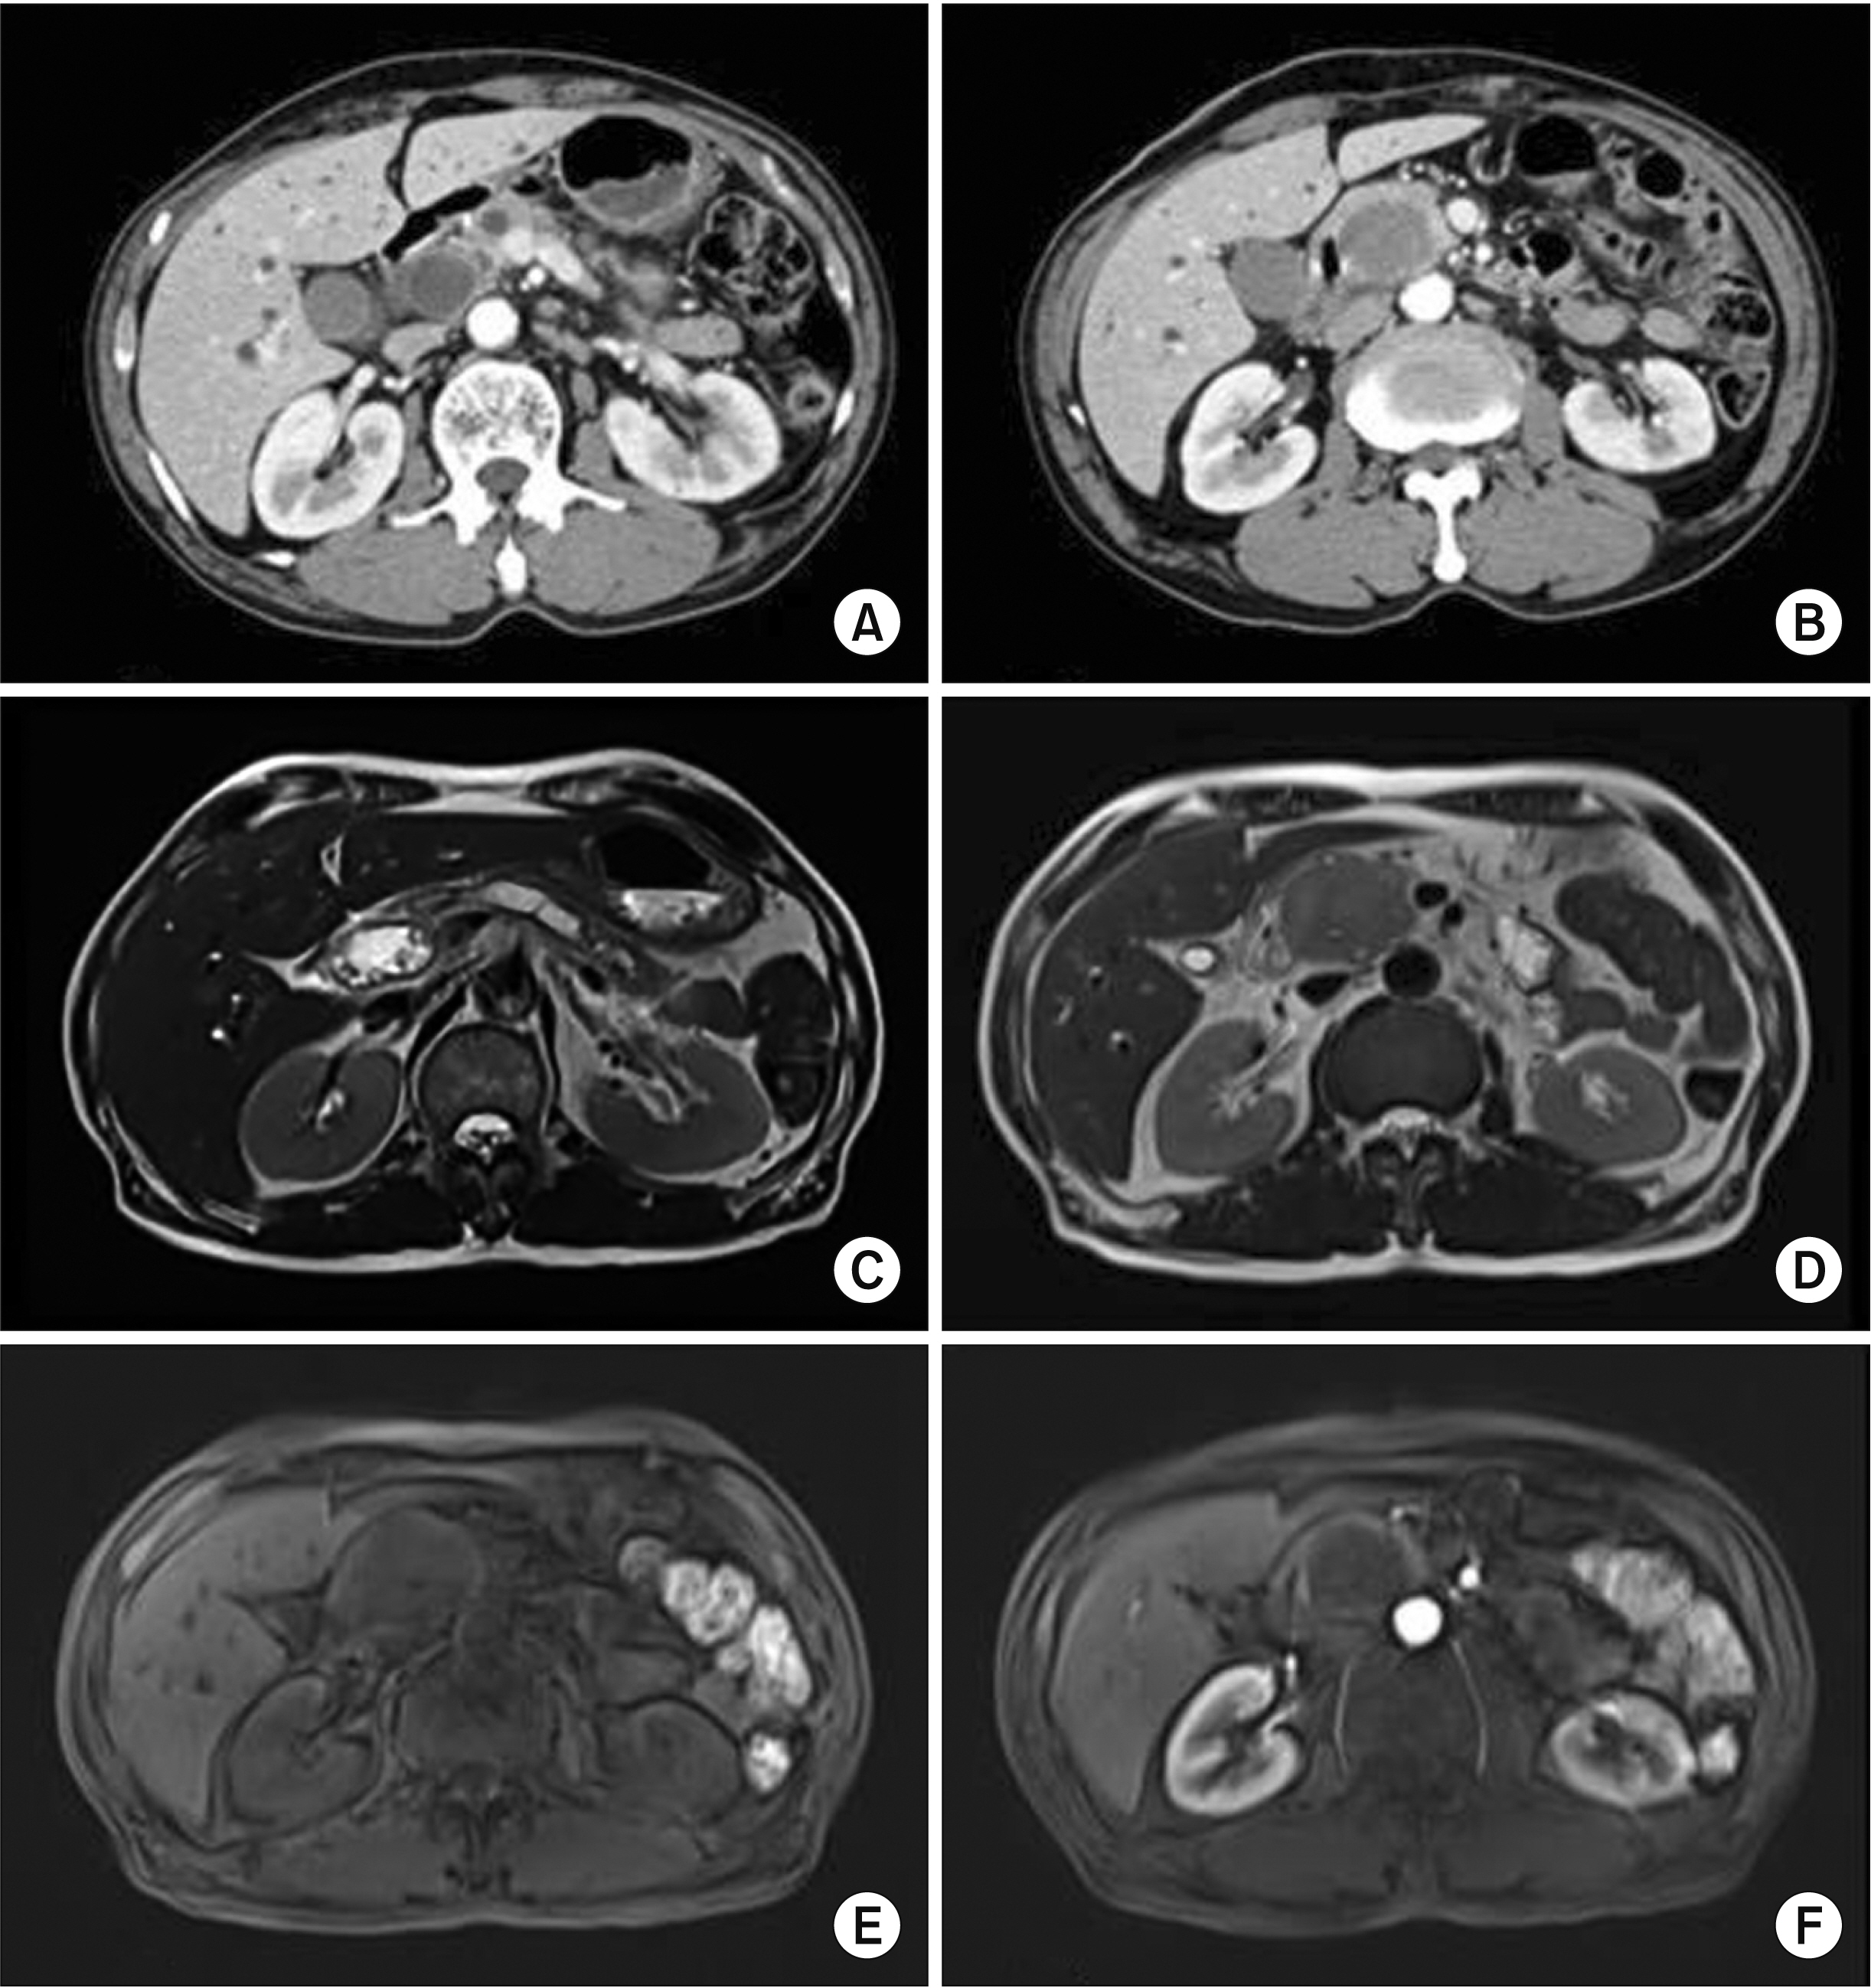

- Bladder cancer is the 9th most frequent cancer worldwide. Its incidence is increasing. The pancreas is an infrequent site of metastasis in relation to any type of malignancy. In this study, we report our experience with a patient who has undergone a pancreaticoduodenectomy for metastatic bladder cancer. A 61-year-old male was admitted with jaundice and pancreas head mass. He underwent robot assisted-cystectomy and ileal conduit for bladder cancer 7 months ago. Initial diagnosis under the imaging study was a resectable pancreas head cancer. However, we did not rule-out a metastatic bladder cancer. He underwent a classic pancreaticoduodenectomy. Based on histologic findings and immunohistochemistry results, a pancreas tumor with 4.9-cm sized metastatic urothelial carcinoma was diagnosed. He experienced no complication. He was discharged 11 days after the surgery. Four cycles of gemcitabine and cisplatin were administered. He remained recurrence-free of tumors for 16 months. Although the benefit of pancreatectomy for patient survival has been reported for metastases from renal cell carcinoma, it is unknown for bladder cancer because of no report. We believe that curative resection for metastasis to pancreas of urothelial carcinoma might be helpful for its management.